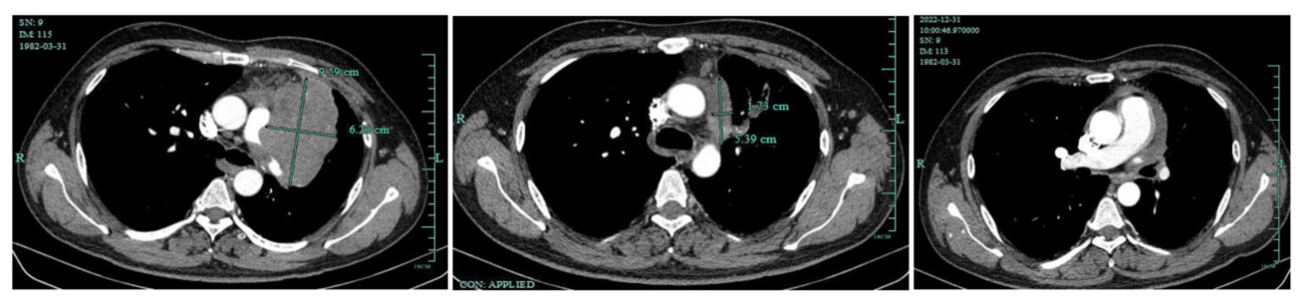

影像学检查图像(基线、2周期后、6周期后原发灶变化)

疗效评估:2周期后肺部病灶显著缩小,肿瘤标志物显著降低,疗效评估为PR,6周期后评估为持续PR。

2022-10-06胸部增强CT:对照2022-07-31CT病灶明显缩小;纵隔及邻近多发血管受侵,较前明显好转,心包积液,较前减少。

2022-12-31胸部增强CT:左上肺癌治疗后复查,对照2022-11-17CT肿块稍缩小,纵隔及邻近多发血管受侵情况较前略好转。两肺下叶炎症,较前新发,建议治疗后复查。原前纵隔结节已消失。心包少量积液。右侧心膈淋巴结稍大,较前片大致相仿。